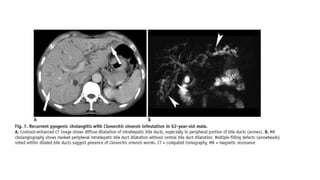

Recurrent pyogenic cholangitis (RPC), previously known as

Oriental cholangiohepatitis, is typically seen in patients who

reside in or who have immigrated from Southeast Asia. It is

characterised by IHD and EHD strictures and dilatation with

pigment stone formation, usually due to parasites, e.g. Clonorchis

sinensis or Ascaris lumbricoides

Recurrent Pyogenic Cholangitis

• Recurrent pyogenic cholangitis is a progressive biliary disease characterized by recurrent

episodes of cholangitis and intrahepatic pigmented stones . RPC is prevalent in Asian countries

and equally affects patients of both sexes

• These patients typically present with abdominal pain, fever, and jaundice (the Charcot triad) and

often have a history of recurrent episodes. The laboratory tests in RPC may demonstrate

leukocytosis and elevated serum bilirubin

• Although the exact pathogenesis of RPC is unknown, strong associations with parasitic

infestation such as Clonorchis sinensis or Ascaris lumbriocoides, portal bacteremia, and

malnutrition. Chronic recurrent infection of the bile ducts is thought to induce biliary stricture,

bile stasis, and pigmented biliary stones.

• The diagnosis of RPC is based on the demographic background, as well as the clinical and

imaging features. Abdominal US in RPC shows bile duct dilatation with increased periportal

echogenicity. The intrahepatic bile duct stones can show various degrees of echogenicity and

posterior shadowing . CT in RPC demonstrates disproportional dilatation of central intrahepatic

ducts and extrahepatic bile ducts with nondilated or minimally dilated peripheral ducts, leading

to decreased arborization and abrupt tapering of bile ducts